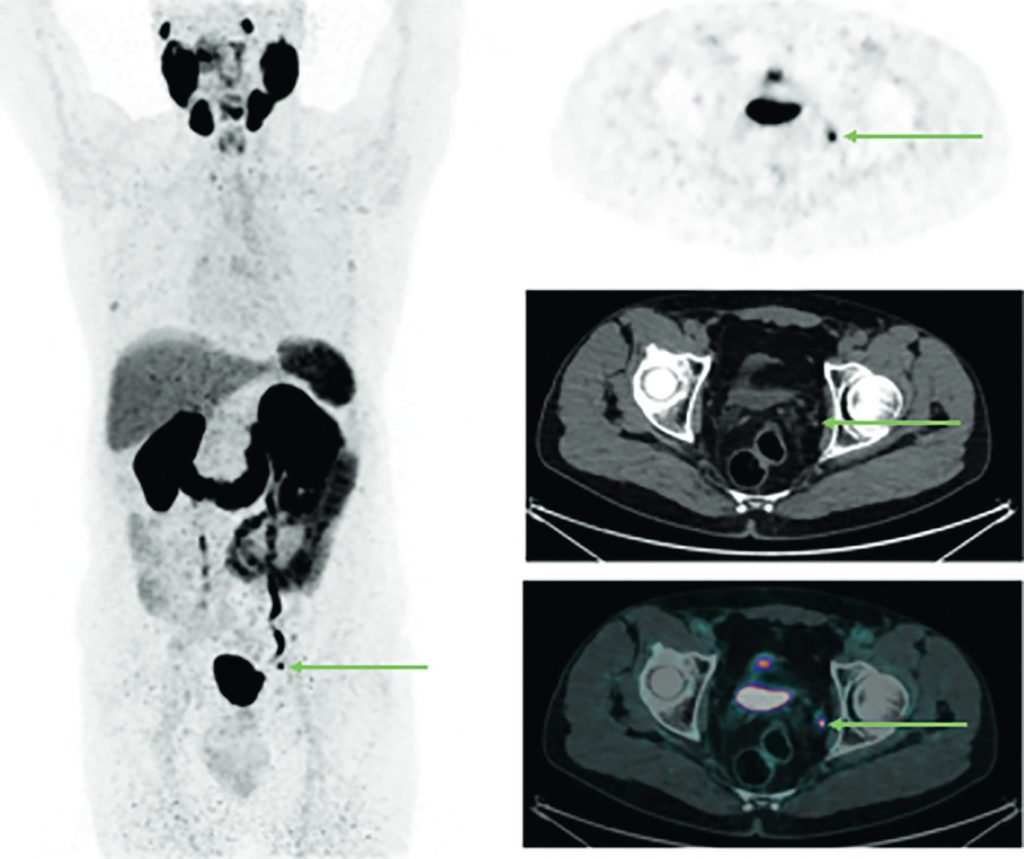

Fig. 30.6 TEP-TDM au 68Ga-PSMA. MIP 3D et coupe axiales TEP, TDM et TEP-TDM centrées sur le pelvis.

Patient présentant une récidive biologique dans un contexte d’adénocarcinome prostatique traité par prostatectomie deux ans auparavant. Images mettant en évidence une hyperfixation pathologique d’un ganglion obturateur gauche, suspecte de récidive isolée.

Source : CERF, CNEBMN, 2022.